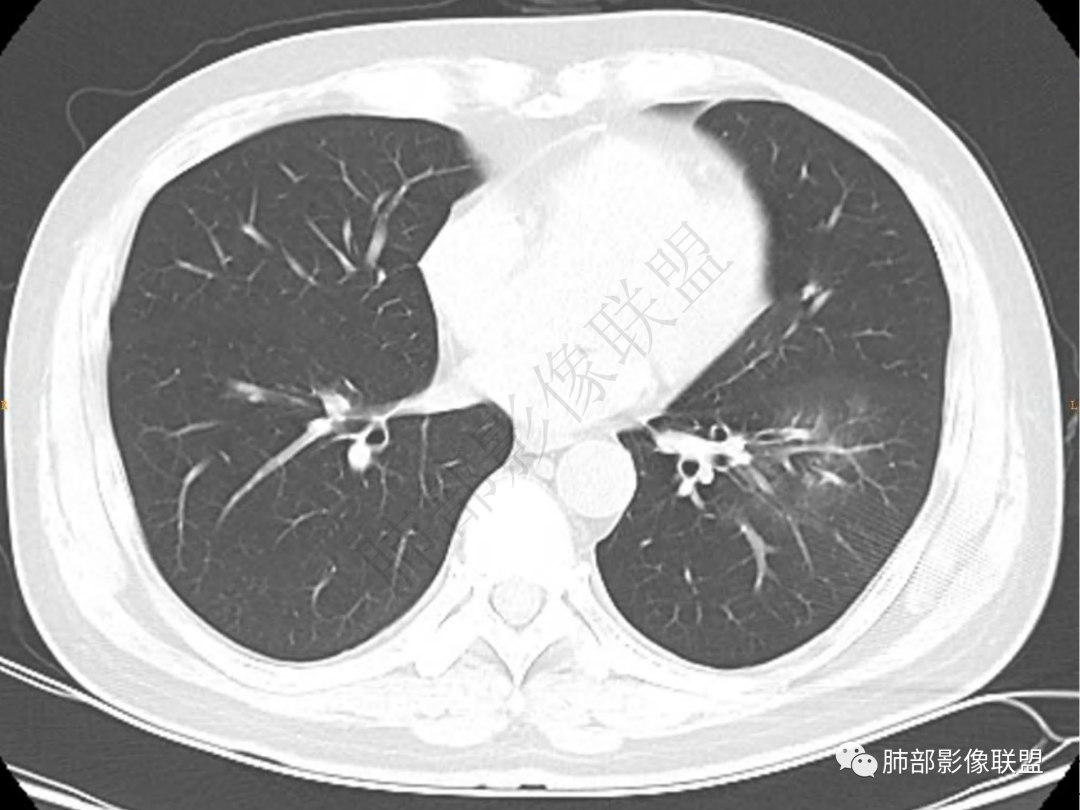

1.中年男性,咳嗽咳痰20余天,间断咯血2周

2.左肺下叶团片影,跨背段及内前基底段,实性部分类椭圆形,密度不甚均匀,可见毛刺及棘状突起,未见典型分叶及胸膜凹陷。病灶上下缘可见相应肺段支气管旁进侧出,管壁轻度增厚,未见狭窄阻塞。

3.周边较大范围磨玻璃影,边界相当模糊,小叶增厚明显。注意叶裂另一侧、左肺舌段亦可见磨玻璃影及增厚的小叶间隔。未见明确卫星病灶。